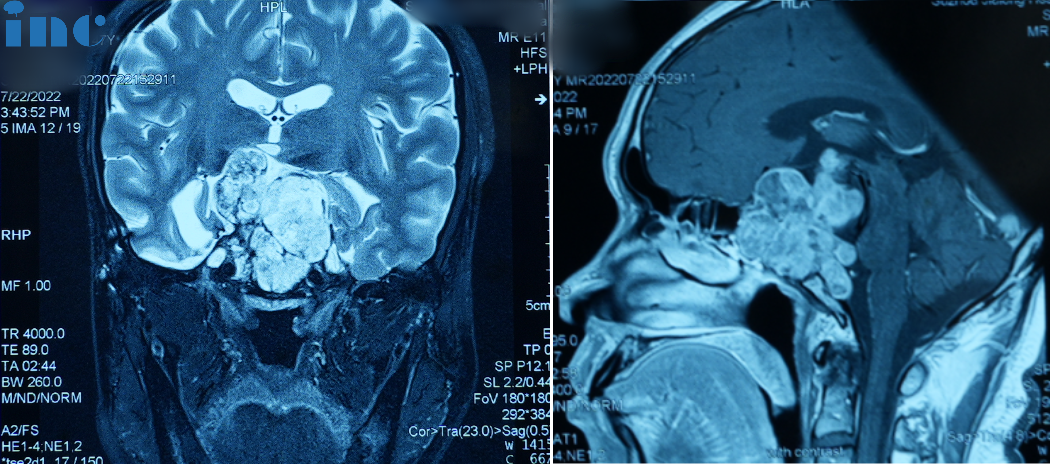

2022年:三次经鼻内镜手术

2022年7月,患者三次出现视力下降/视野缺损症状,磁共振检查再次提示“鞍区肿瘤复发”。

因患者不想再接受开颅手术,10月8日全麻下行经鼻神经内镜下肿瘤切除术。术后病理为“脊索瘤(复发)”。术后出现嗜睡、精神萎靡等内分泌功能紊乱症状,同时伴脑积水。遂于11月19日行脑脊液V-P分流术,后症状缓解消失。

2023年1月底,患者四次出现上述症状,4月份开始自感四肢肢力下降,虽可自行站立和行走,但自感不稳。

术前症状:视力下降,视野缺损,言语不清,吞咽困难,呛咳,眼球活动障碍,走路不稳,上肢无力,嘴角抽搐,体重下降。